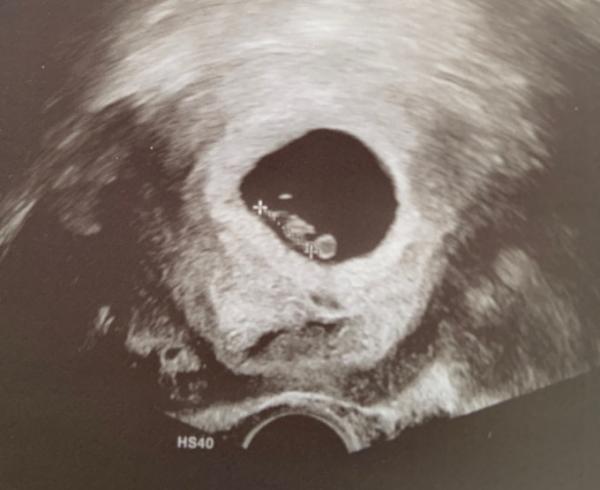

Hallo ihr Lieben, ich wollte ein kleines Update meines Mini Eckenhockers geben. Wir waren am Donnerstag da und sofort konnte man den kleinen “Little” mit schlagenden Herzchen sehen das Mini Mäuschen ist ein klein wenig kleiner für 8. Woche aber sonst alles super. Endlich ganz mal direkt positive News ich finde, man kann seitliche Ansätze von Armen erkennen oder? Das untere ist nicht der Kopf sondern der Dottersack. Hab’s nicht erkannt

Das Bild fehlte noch